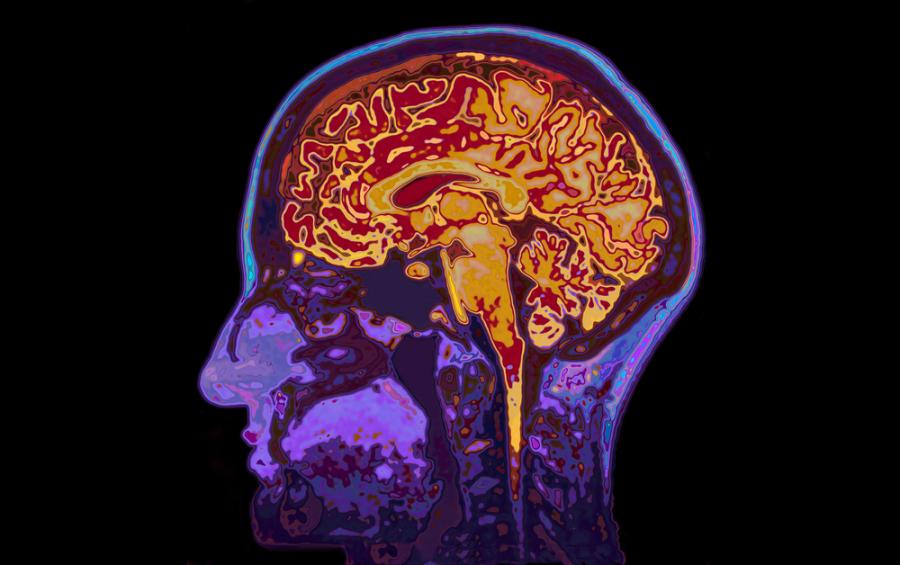

Ето как мозъкът реагира на самотата

Контактът с други човешки същества е полезен не само от психологическа гледна точка. Той помага и на еволюцията. Групата от хора по-лесно е намирала подслон и храна, отколкото отделен човек е могъл. Инстинктът да търсим комфорт от присъствието си в група също е дълбоко вкоренен. Когато бъдем лишени от контакт често ставаме самотни, разстроени и нещастни. Екип от учени от Масачузецкия технологичен институт (МИТ) идентифицира частта от мозъка, която отговаря за чувството на самота – дорзалното ядро в мозъчния ствол (ГРЦ). Там се съдържат клетъчни вериги, които според изследователите са отговорни за желанието за социализация след период на изолация.